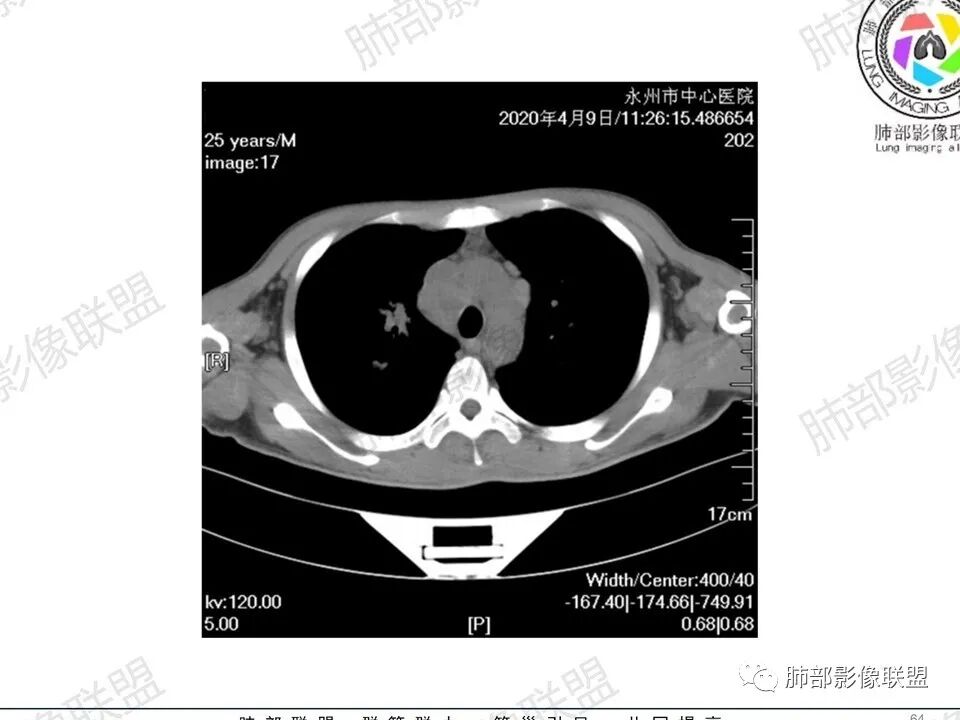

3、影像表现:双肺散在斑片影及结节影,部分结节内可见血管穿行,斑片影沿支气管血管束分布,近胸膜侧病变收缩不明显。部分中央淋巴间质增厚,小叶间隔增厚。病灶内支气管穿行,部分支气管略扩张。局部小结节呈串珠样改变。纵隔、肺门区、锁骨上及腋窝淋淋巴结肿大,部分有融合。心腔低密度。脾大。

5.双肺门及纵隔淋巴结显著增大,这改变相当显眼。这里强调“双肺门”及“多发”!

增大的淋巴结密度偏低且均匀。此外患者有体表淋巴结增大。

6.心腔密度减低。提示可能存在贫血。

1.临床表现明显,纵隔及双肺门淋巴结显著肿大,临床最为担心的还是淋巴瘤!

尤其患者有贫血及脾脏增大,又有体表淋巴结增大时,这也是临床相对常见的情形。